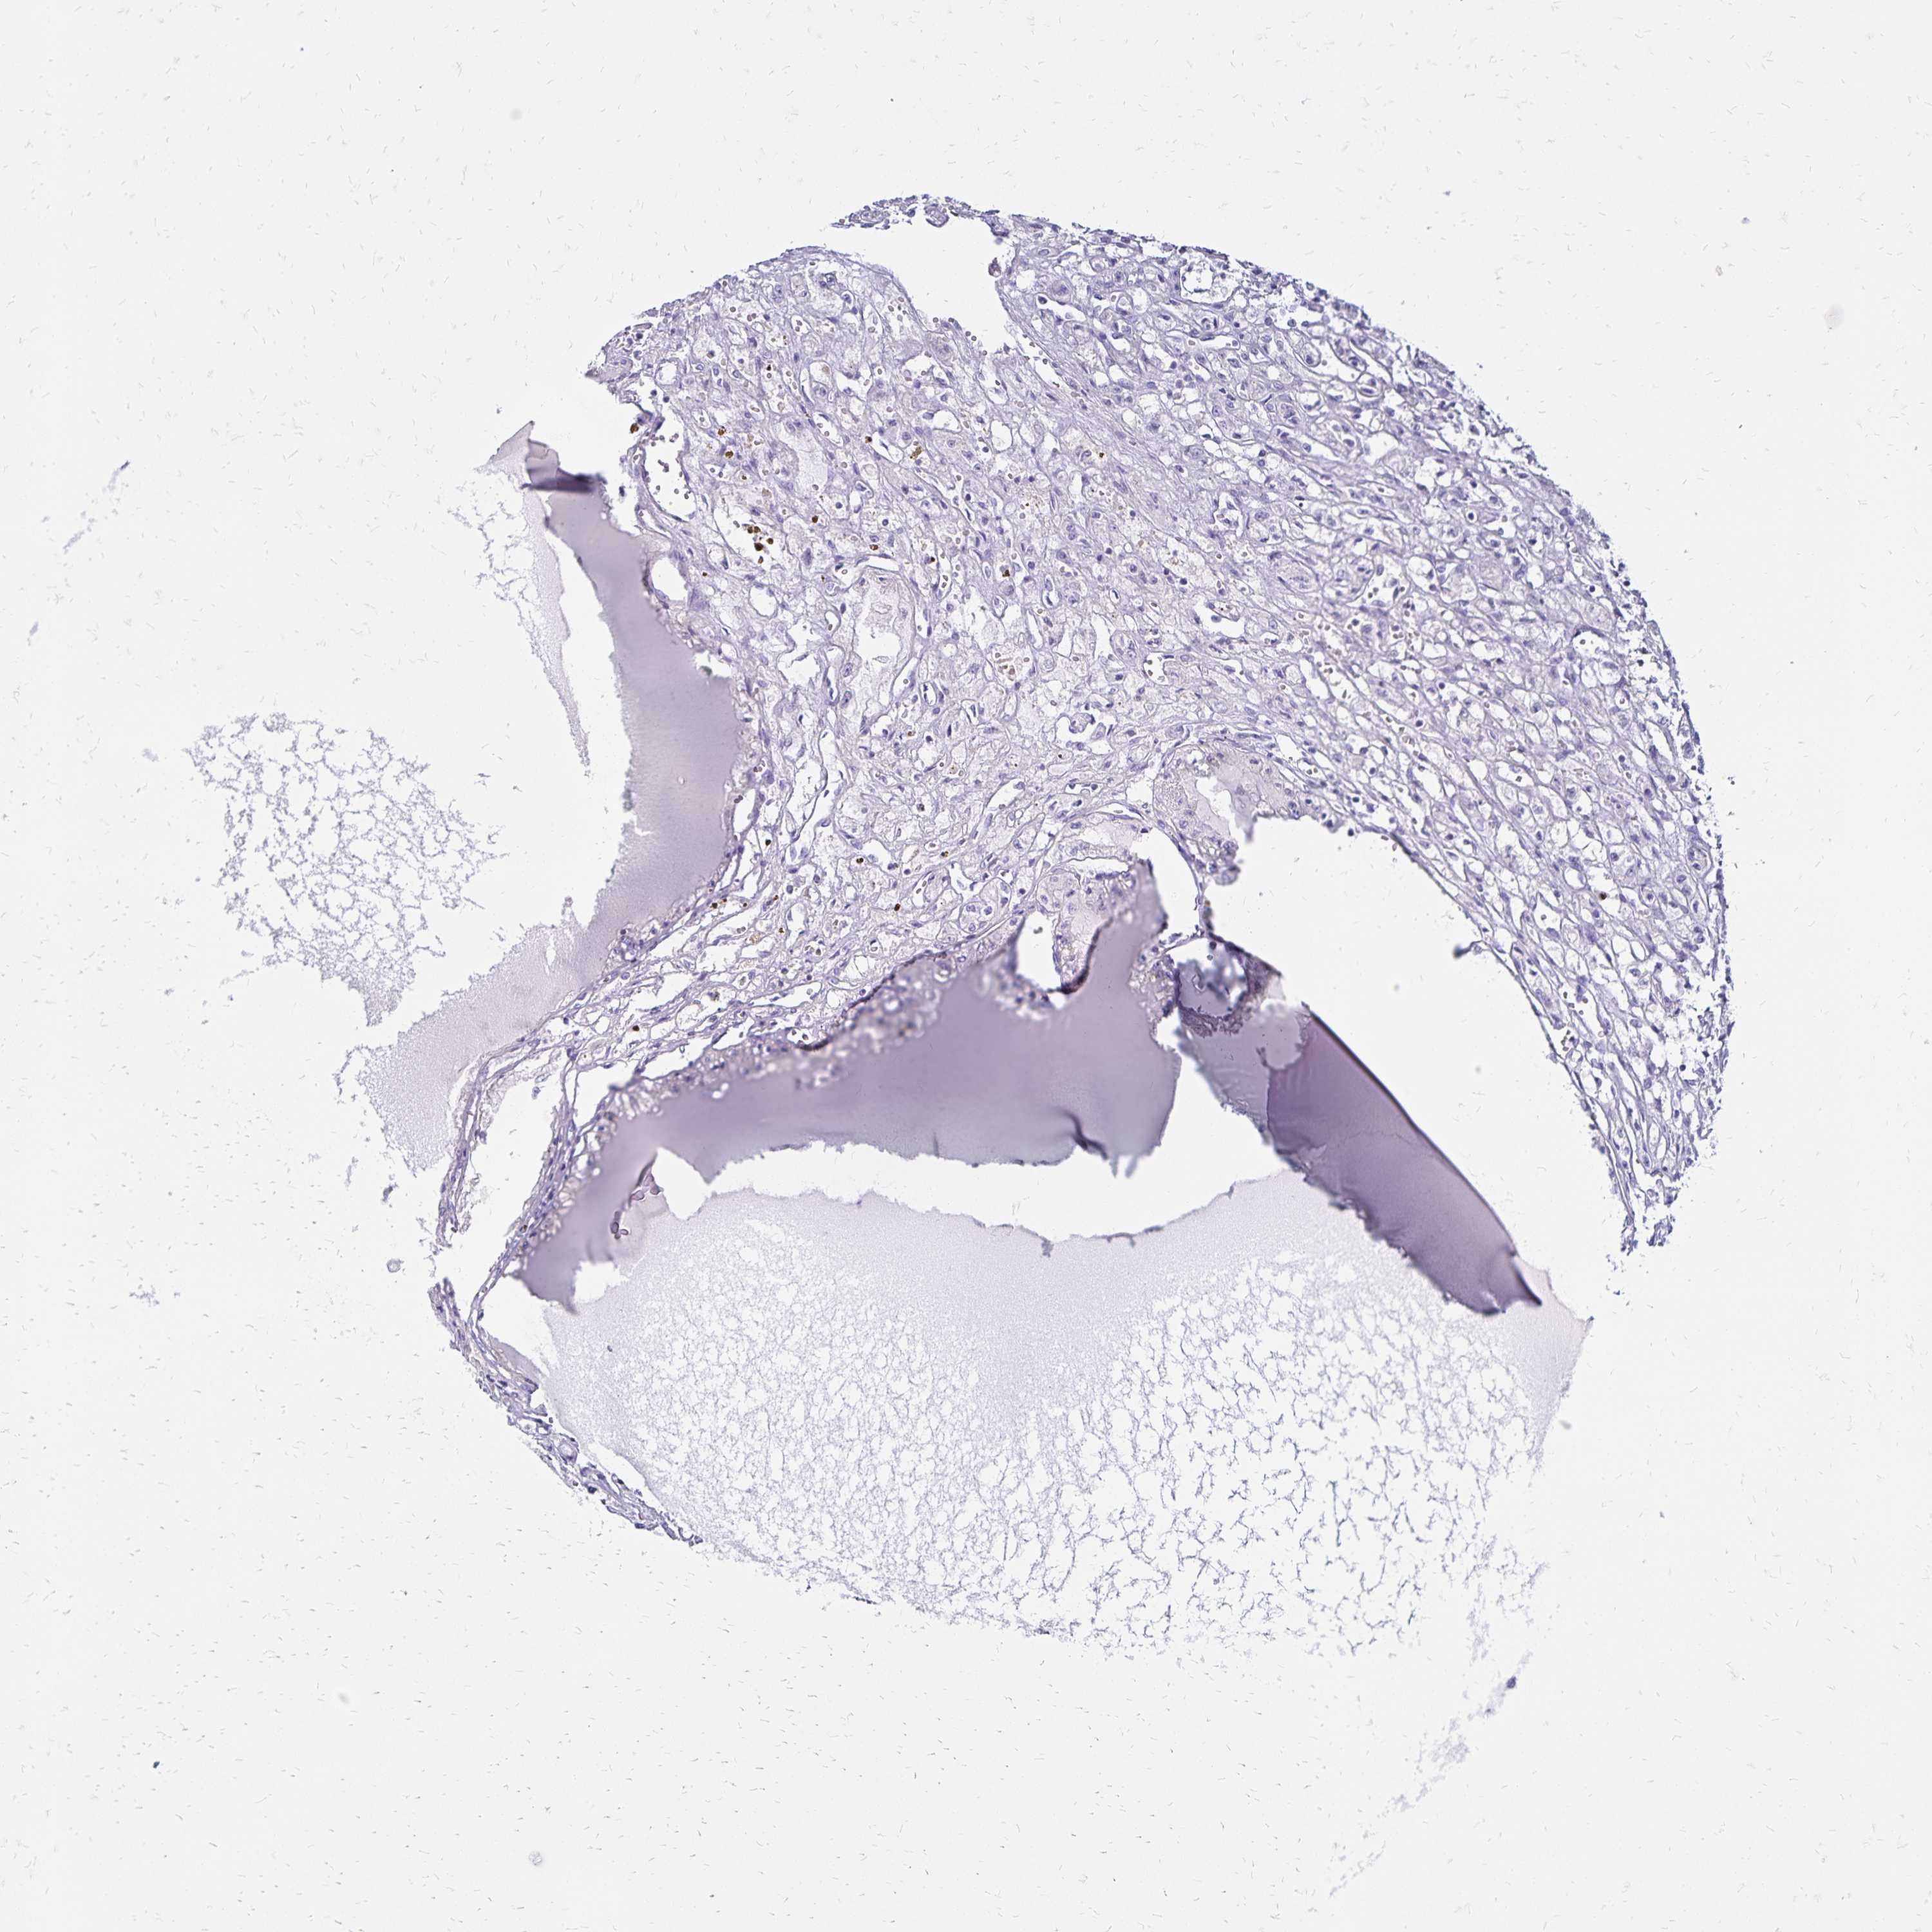

KIDNEY RENAL CLEAR CELL CARCINOMA (VALIDATION) - Interactive survival scatter ploti

The Survival Scatter plot shows the clinical status (i.e. dead or alive) for all individuals in the patient cohort, based on the same data that underlies the corresponding Kaplan-Meier plots. Patients that are alive at last time for follow-up are shown in blue and patients who have died during the study are shown in red.

The x-axis shows the expression levels (FPKM) of the investigated gene in the tumor tissue at the time of diagnosis. The y-axis shows the follow-up time after diagnosis (years). Both axes are complimented with kernel density curves demonstrating the data density over the axes. The top density plot shows the expression levels (FPKM) distribution among dead (red) and alive patients (blue). The right density plot shows the data density of the survived years of dead patients with high and low expression levels respectively, stratified using the cutoff indicated by the vertical dashed line through the Survival Scatter plot. This cutoff is automatically defined based on the FPKM cutoff that minimizes the p-score. The cutoff can be changed by dragging the vertical line or by entering a cutoff value in the square labeled "Current cut-off".

Under the Survival Scatter plot the p-score landscape (black curve; left axis) is shown together with dead median separation (red curve; right axis). Dead median separation is the difference in median mRNA expression between patients who have died with high and low expression, respectively. It is calculated as follows: median FPKM expression of dead patients with high expression - median FPKM expression of dead patients with low expression. This is intended to aid the user in visually exploring custom cutoffs and the associated p-scores and dead median separation.

Individual patient data is displayed and can be filtered by clicking on one or more of the category buttons on the top of the page. Categories describing expression level and patient information include: high, low, alive, dead, female, male and tumor stages. The scale of the x-axis can be toggled between linear and log-scale by clicking on the "x log" button. Mouse-over function shows TCGA ID, patient information and mRNA expression (FPKM) for each patient.

& Survival analysisi

Kaplan-Meier plots summarize results from analysis of correlation between mRNA expression level and patient survival. Patients were divided based on level of expression into one of the two groups "low" (under cut off) or "high" (over cut off). X-axis shows time for survival (years) and y-axis shows the probability of survival, where 1.0 corresponds to 100 percent.

CCDC39 is not prognostic in Kidney Renal Clear Cell Carcinoma (validation)

Best expression cut offi

: 6.39

Average pTPM 5.5

Number of samples 100